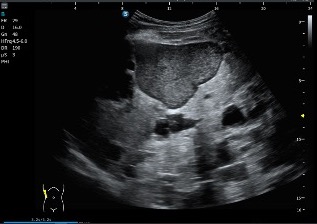

Durante el mismo estudio hepático se identifica una lesión que no sigue exactamente el comportamiento del resto:

- Más ecogénica

- Con contenido interno

- No completamente anecoica

El radiólogo la interpreta como posible quiste hepático complicado, como ves en las imágenes siguientes, siempre, documentar lo mejor posible.

Conviene recordar que en los cuadros de poliquistosis hepática o hepatorrenal algunos quistes pueden sangrar, infectarse o modificar su contenido, perdiendo el aspecto anecoico puro y mostrando ecos internos o mayor ecogenicidad. Debemos estar muy atentos a cualquier cambio y mirar muy bien gastando tiempo en revisar todo.